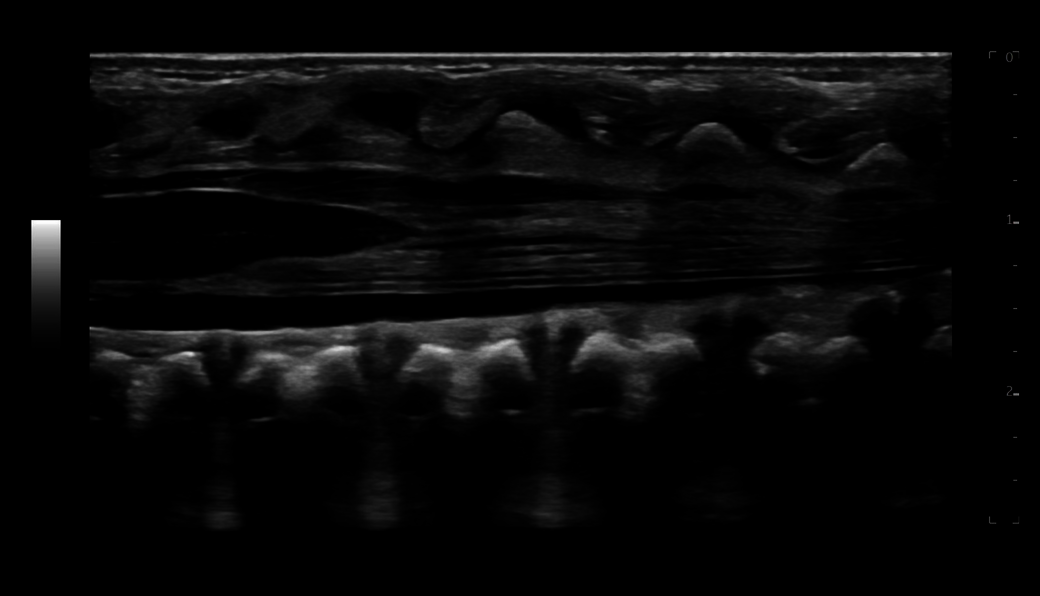

B-Flow imaging - non-Doppler technique - enables direct, real-time visualization of blood flow echoes with no vessel wall overlap to obscure details

XDclear probes combine innovative technologies that help maximize the potential acoustics to measurably increase penetration and deliver high definition resolution throughout the image.

Matrix probes provide multiple rows of crystals, allowing great spatial resolution and image uniformity from near to far field.

Combining XDclear and Matrix technologies, the ML4-20-D delivers exceptional resolution and penetration for confident imaging.

The L6-24-D high-frequency probe provides outstanding detail and clarity for superficial structures, powered by XDclear technology.